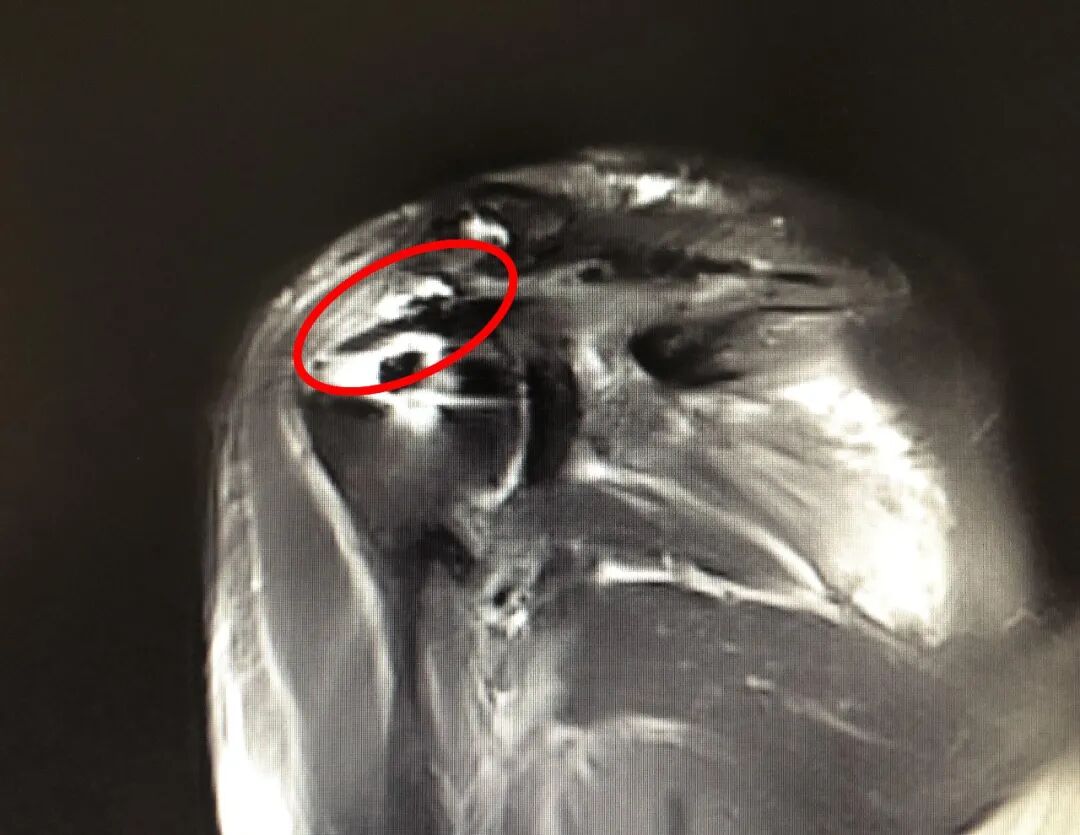

58岁的田女士四年前右肩部受过伤,最近右肩关节疼得厉害,胳膊也无法抬起,来到我院骨科就诊,磁共振检查显示“巨大肩袖撕裂,肩袖严重回缩”。 术前影像资料 经过充分术前讨论,骨科二病区医疗团队决定为患者实施肩关节镜微创治疗。术中探查发现,患者肩袖回缩严重,不适合直接修复,遂采用“Chinese Way”术式完成肩关节镜下肌腱重建。术后三个月复查,患者右臂活动自如,肌腱位置良好。 术后3个月复查影像资料 骨科二病区主治医师孙卓伟介绍:“不可修复的巨大肩袖撕裂,治疗时需要考虑很多因素,由于肌腱变性、肌肉脂肪浸润、肌腱的过度回缩导致肌腱质量比较差,手术难度系数极大,怎样在关节镜下缝合肌腱以达到更好的效果,对于手术医师来说也充满了挑战。” 医师提醒 肩袖撕裂后首先要减少导致疼痛的动作,不刺激患处,若疼痛时间较长,症状严重,建议尽快来院就诊,尽早恢复肩关节功能。 关节镜微创技术相较于传统手术,具有切口小、感染率低、恢复快,住院时间短等优点。 骨科二病区2019年起开展肩关节镜微创技术,截至目前开展手术100余例,均取得了良好效果。科室独立开展巨大肩袖撕裂、肩峰撞击、关节内游离体、钙化性肌腱炎,肱二头肌病变等肩关节疾病手术诊疗。 联系电话: 0533-8228176 就诊地址: 门诊楼二楼外科诊区 住院部7楼西